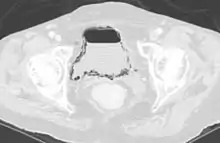

Cystite compliquée d'un emphysème